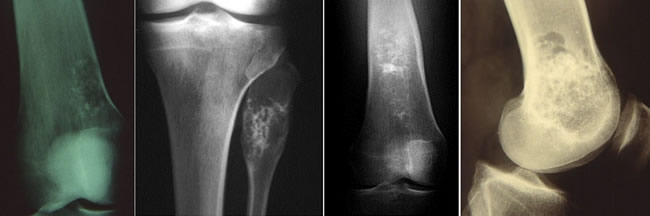

Radiologie : les calcifications

Siège métaphysaire ou métaphyso-diaphysaire.

Géode claire, homogène, arrondie, nette.

Trabéculations fines ou petites opacités punctiformes.

Dans les enchondromes, l'imagerie montre des images floconneuses à l'intérieur de la cavité médullaire.

Ces calcifications augmentent avec l'age de la tumeur.

Radiologie des chondromes périphériques

Métaphyse, métaphyso-diaphyse

Trabéculations fines ou petites opacités.

Corticale soufflée.

Excroissance inhomogène à base d'implantation large (cloison corticale).